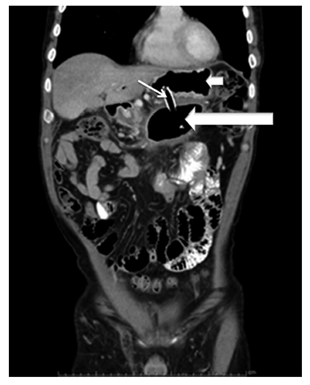

5 pacientes eran mujeres (50%). El rango de edad de presentación estaba entre 11 y 68 años de edad. El diámetro promedio fue 10,6 cm (5-22 cm). El 90% de los casos comprometía el cuerpo de páncreas. Se logró implantar exitosamente un stent transmural (cistogastrostomía) en 9 pacientes (90%) (Figura 2), en 6 pacientes se colocó solo el stent metálico autoexpandible parcial o totalmente recubierto y en 3 pacientes se colocó el stent metálico y en su interior un stent doble cola de cerdo de 10 Fr, en 1 paciente se realizó el drenaje por aspiración con resolución del 95% del tamaño de la lesión dado que el pseudoquiste fue de 5 cm. Un paciente presentó durante el procedimiento liberación del stent metálico dentro de la cavidad del pseudoquiste, requirió la colocación de otro stent metálico y en un segundo tiempo endoscópico, 48 horas después, se retiró el stent entrando a la cavidad con un endoscopio pediátrico y luego se reposicionó el stent migrado.

Según los hallazgos ecoendoscópicos, el 80% de las lesiones correspondía a pseudoquiste pancreático y el 20% a colección líquida con necrosis pancreática amurallada (walled-off). No hubo muertes asociadas con el procedimiento. Se realizó control tomográfico abdominal 6 semanas después del procedimiento (Figura 3) en el que se evidenció una resolución completa del pseudoquiste en el 90% de los casos sin complicaciones. Todos los pacientes con cistogastrostomía resolvieron completamente la lesión, la paciente a quien se realizó drenaje por aspiración presentó recidiva del pseudoquiste a nivel del cuerpo del páncreas a las 4 semanas.